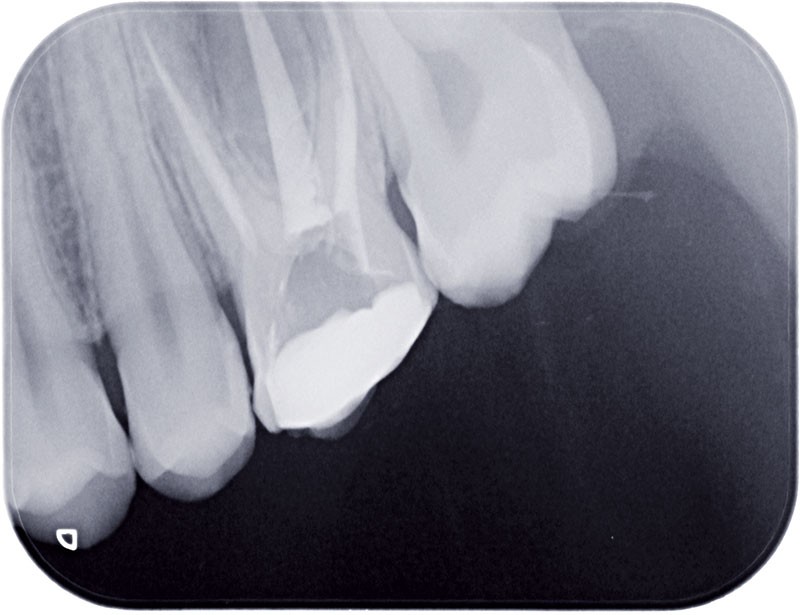

• Endo-buccal : Younesse présente un contrôle de plaque dentaire insuffisant, la persistance de 53 et 63, des soins en cours de réalisation sur 26 et 36, un encombrement maxillo-mandibulaire avec infravestibulotopie de 23 et une suspicion d’inclusion de 13 sur un schéma de Classe II subdivision droite (fig. 3 à 7).

La reconstruction 3D confirme la position vestibulaire de la 13 avec appui coronaire sur la racine de 12 (fig. 8 et 9).